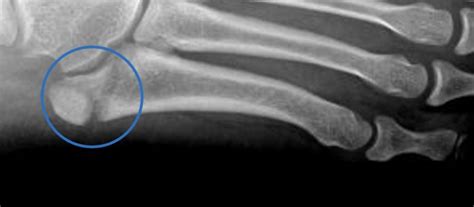

WebA base do quinto metatarsal é dividida em três zonas de fratura. As fraturas da zona 1 são fraturas por avulsão que ocorrem na ponta da base do quinto metatarsal. Estas fraturas. WebAinda assim, a base do 5º metatarso é dividida em 3 zonas, sendo essa a região mais comumente fraturada. Desse modo, essas 3 zonas são: ZONA 1: é uma.

WebComo é chamada a fratura da base do quinto metatarso do pé? As fraturas da base são às vezes chamadas de fraturas de dançarina ou pseudo-Jones. O mecanismo traumático é. WebA fratura mais comum no quinto metatarso, pode ocorrer por trauma direto ou por torção no pé. Laudo on-line. Pacientes; Médicos (48) 3631-1400 (48) 98871-4304 . Horário:.

WebFratura do Quinto Metatarso (Pé): Sintomas e Complicações. Encontre 26 perguntas relacionadas Como saber se você tem uma microfratura? ... Como é chamada a fratura. WebAs fraturas do 5º metatarsiano podem se dar por três formas principais: – Por avulsão, quando ocorre uma entorse do tornozelo. – Fratura de Jones: pode ser aguda ou por.

WebFratura da base do 5º metatarso WebFratura do 5º Metatarso. Relato de caso: Paciente do sexo masculino, 33 anos, sofreu acidente de moto X carro no dia 16/12/2018, na rodovia em alta velocidade,. WebSão Paulo. Fraturas da base do quinto metatarso , quando sem desvio ou estáveis, são de tratamento conservador com período de imobilização aproximado de 6 semanas. Casos.